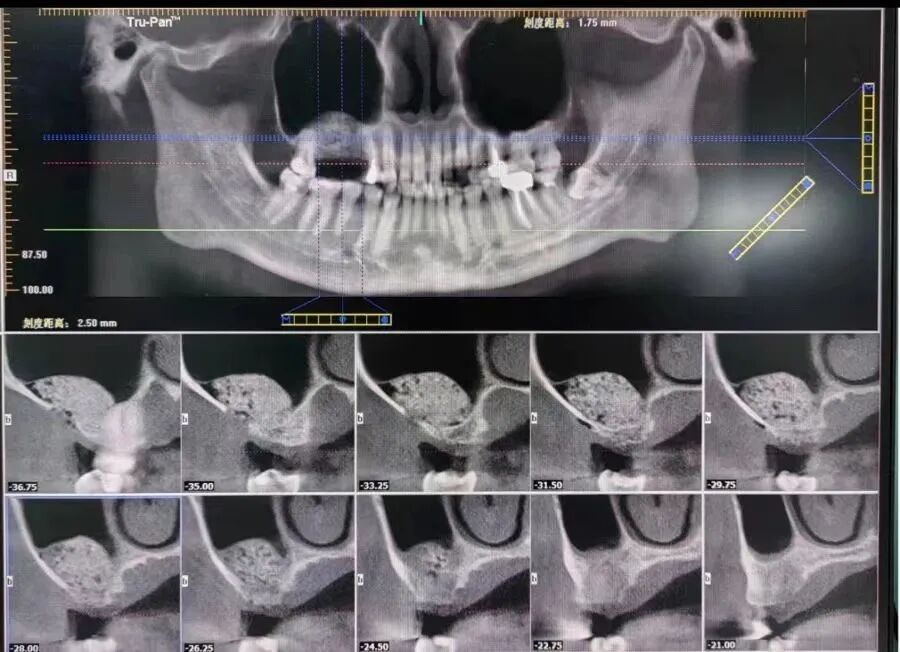

手術(shù)后CT片